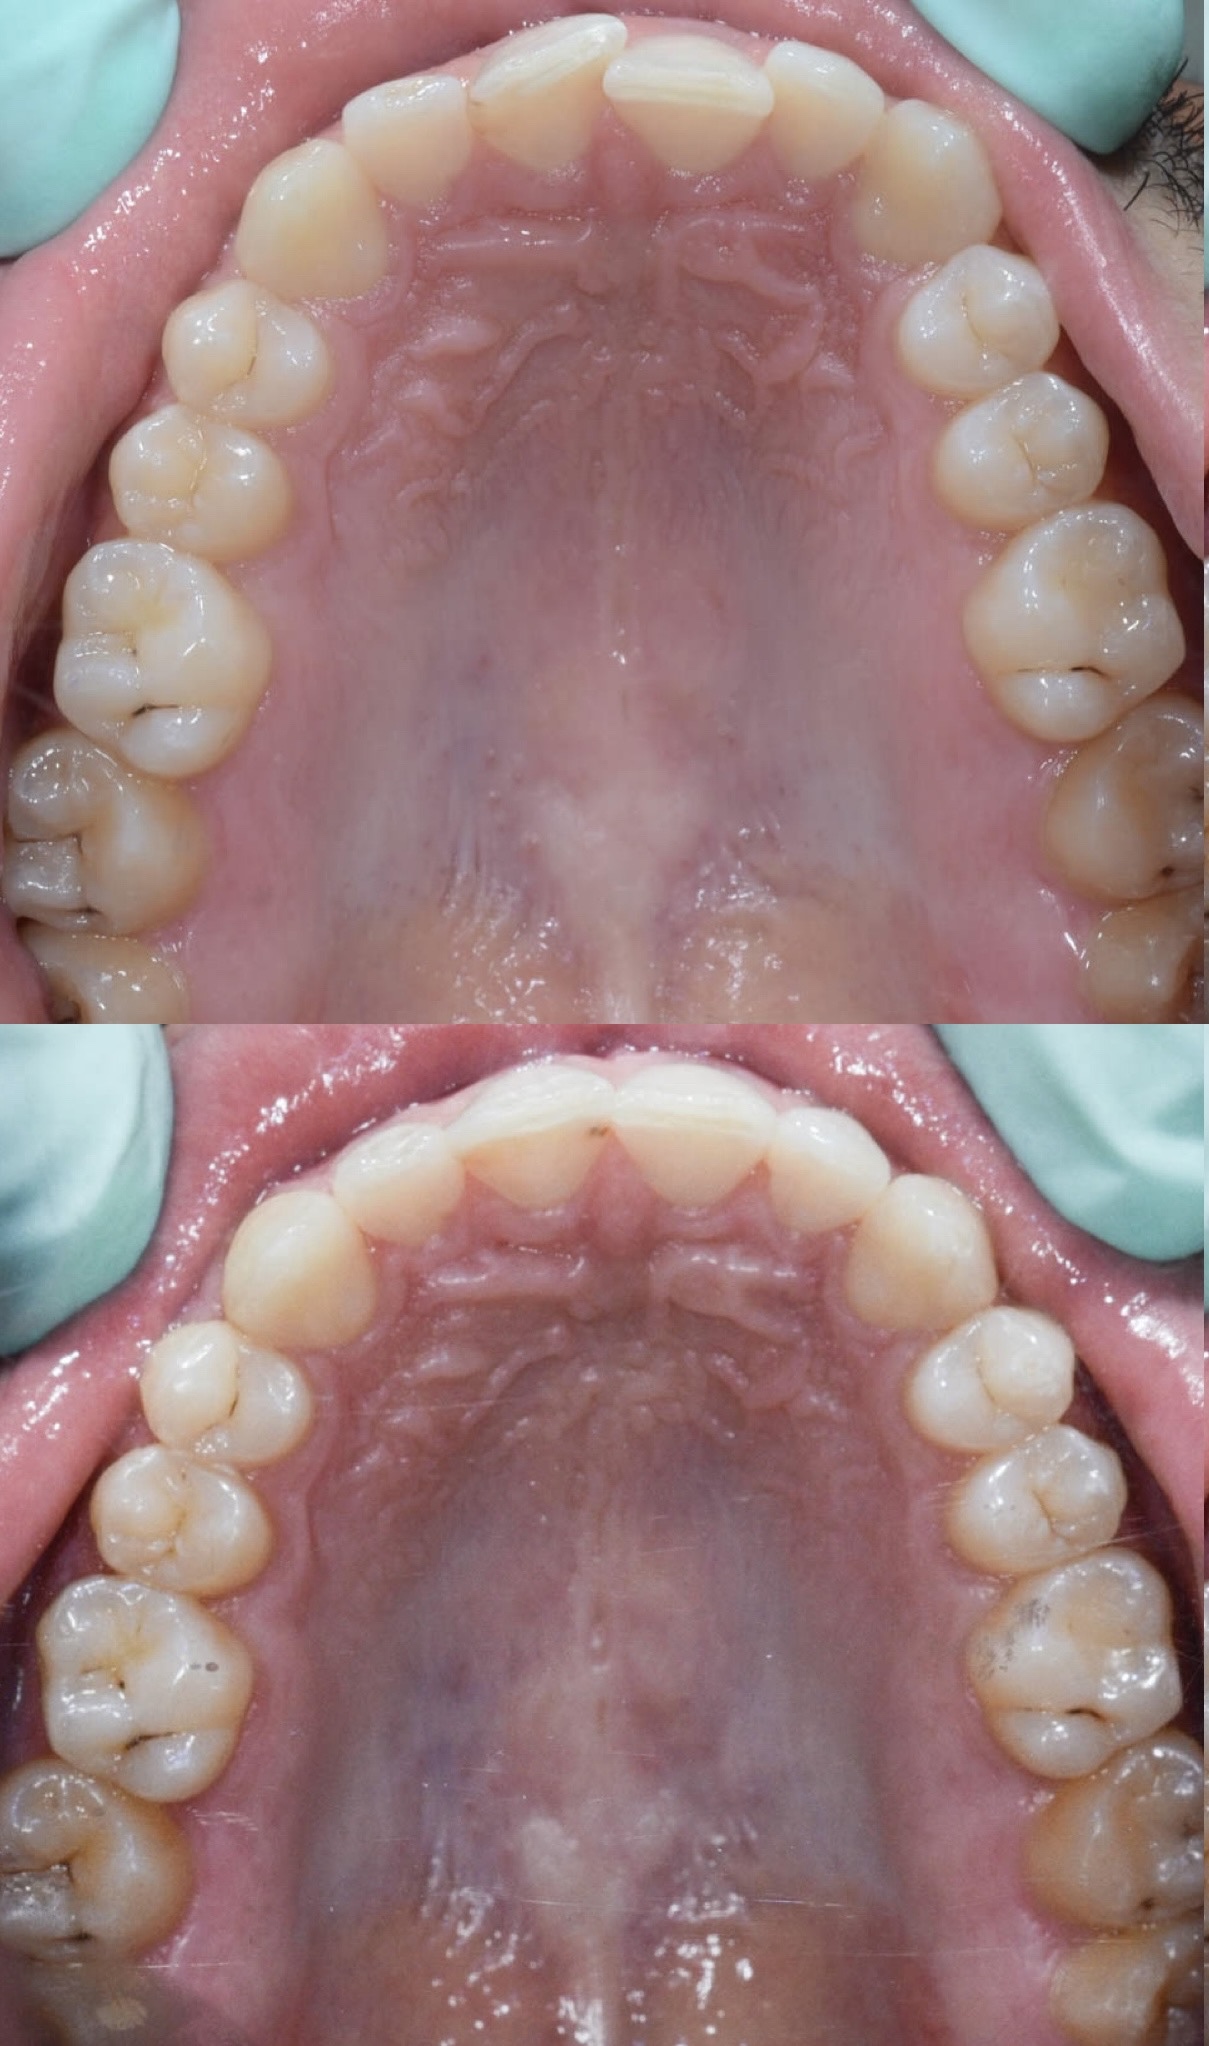

Slučaj 3: ispravljanje kompresije Invisalign full terapijom

Slučaj 4: ispravljanje kompresije Invisalign full terapijom

Slučaj 5: ispravljanje kompresije i križnog zagriza Invisalign full terapijom

Slučaj 6: ispravljanje kompresije i dubokog zagriza Invisalign full terapijom

Slučaj 7: ortodontska predprotetska terapija Invisalign full